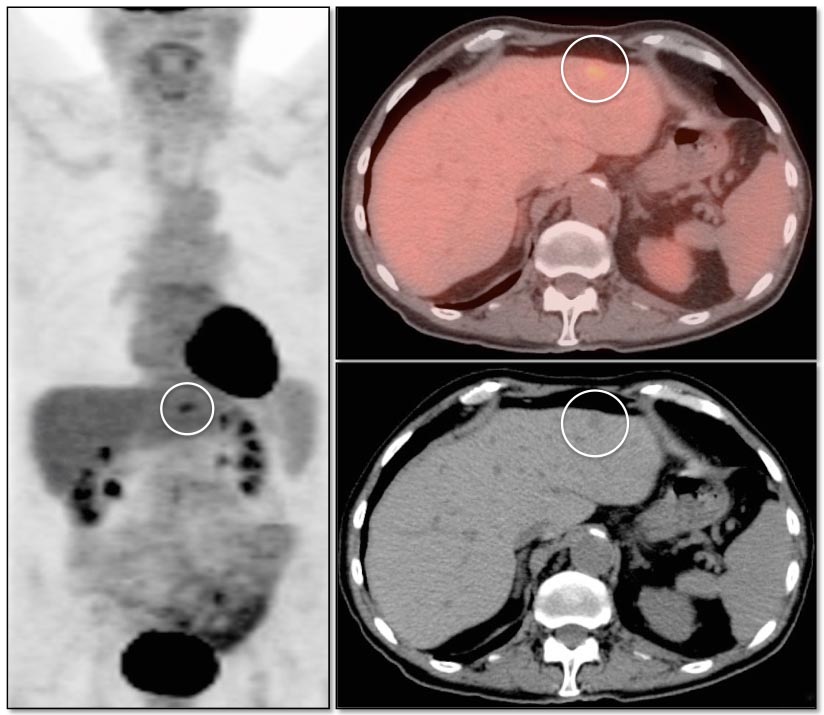

Focal increased FDG uptake in the liver is always highly suspicious for malignancy. Very commonly, these malignant lesions may be poorly delineated on the co-registered CT images due to the lack of intravenous contrast administration.